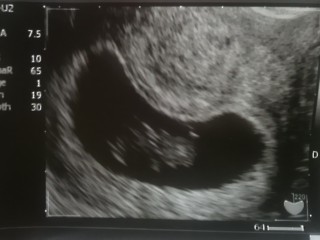

足がピクピクしていた! 初めて動いてるのを見ることができました♪ 大きさは23.0mmでした~!